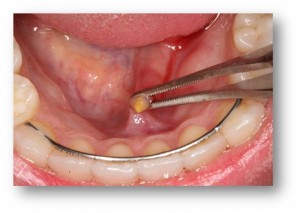

Главным диагностическим симптомом является обнаружение слюнного камня, боль, возникающая при приеме пищи, связанная с нарушением оттока слюны. Сиалодохит и сиаладенит являются сопутствующими симптомами. Перечисленные симптомы нарастают с возрастом ребенка.

Диагноз ставится на основании общих клинических методов обследования (жалобы, анамнез, осмотр ребенка, пальпация железы, визуальное исследование секрета, клинический анализ крови и мочи), рентгенологического исследования ПЧСЖ, эхографии.